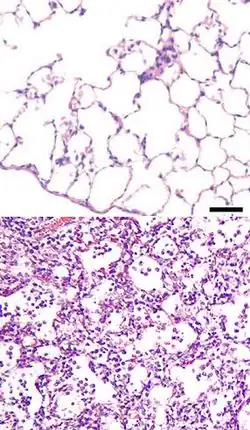

Oft besteht die Reaktion aus einer Abstoßung eines Teils des kranken Gewebes durch Nekrose oder Apoptose und anschließender Neubildung von Zellen zur Reparation des Gewebeschadens. Die Abstoßung von Zellen dient bei Hautzellen unter anderem dem Schutz des darunterliegenden Gewebes. Eine Entzündung kann lokal in einem (kleinen) umschriebenen Gebiet auftreten oder den ganzen Körper betreffen. Beispiele für lokalisierte Entzündungen sind z. B. die Enteritis (Entzündung des Darms), die Kolitis (Entzündung des Grimmdarms), die Gastritis (Entzündung des Magens), die Arthritis (Gelenkentzündung), die Myokarditis (Herzmuskelentzündung), die Dermatitis (Hautentzündung) und die Otitis (Ohrenentzündung). Eine sprachliche Ausnahme bildet die Pneumonie (Lungenentzündung), bei der die Endung „-itis“ fehlt (allerdings wird selten auch die Form Pneumonitis verwendet).